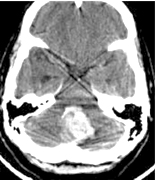

| Figure 5: Acute cerebellar haematoma |

- Acute cerebellar haematoma larger than 3cm (Figure 5).

- Deep seated basal ganglia haematoma in the non-dominant hemisphere producing progressive deficit in the subacute phase.